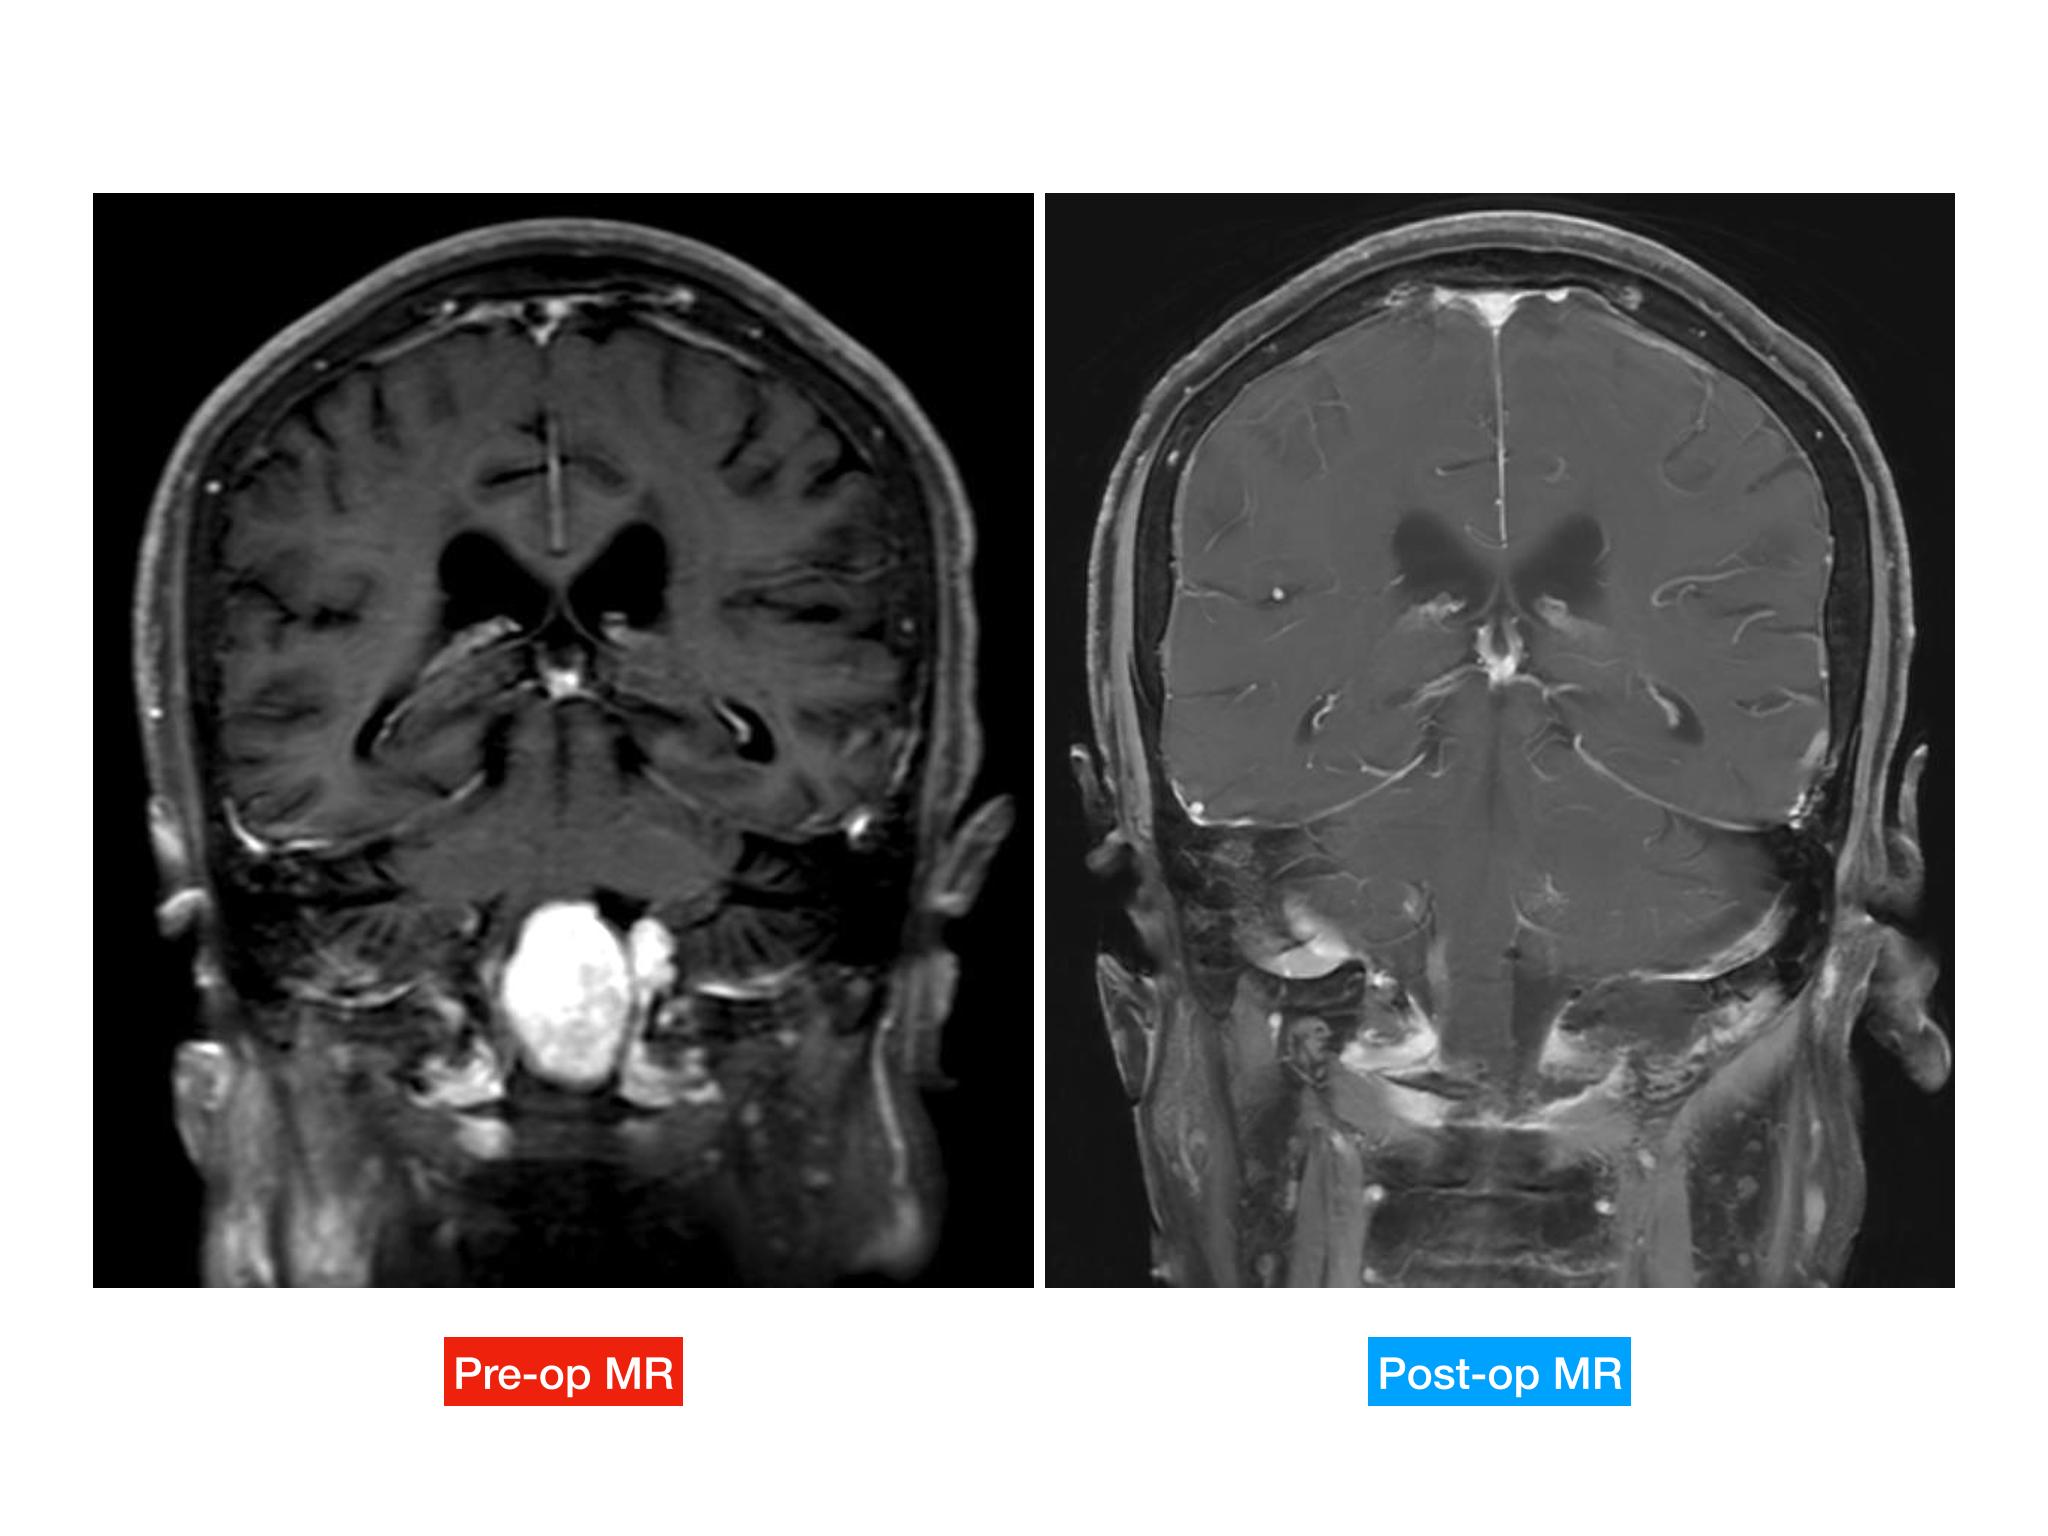

汇报一例后颅底肿瘤手术。为枕骨大孔巨大腹侧型脑膜瘤,该患者高龄,同时合并肺Ca,术前2周急性加重,枕骨大孔疝前期表现,术前已有延髓压迫及后组颅神经麻痹表现。经详细评估后采用远外侧经髁窝入路,最大化显露,重点保护延髓、后组颅神经,尽可能“零骚扰”。术中肿瘤质地韧,血供一般,与肿瘤上极与后组颅神经黏连紧密,最终99%切除,残留约1%,术后顺利康复出院,无新发症状,为后续进行肺部病变化疗创造有利条件。